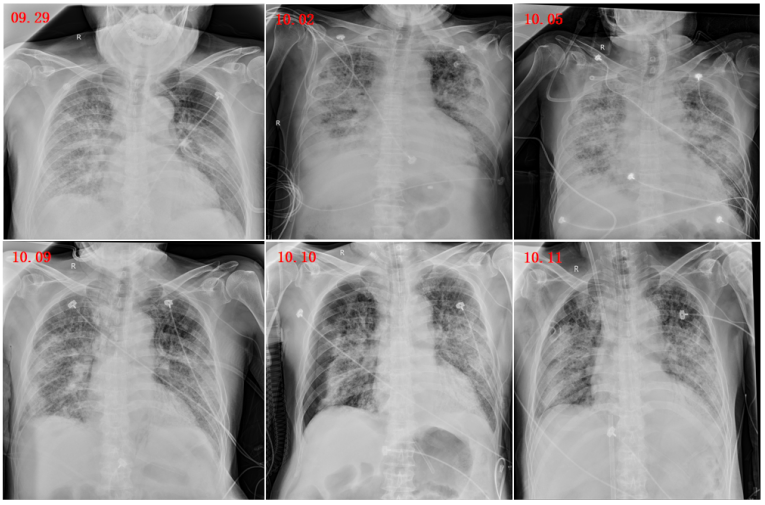

10月10日复查床旁胸片:两肺间质性肺炎并感染,病变范围较10月9日变化不大,右侧新增气胸(肺组织压缩40%)。立即予胸腔闭式引流术+气管镜引导下经鼻气管插管。

图片

图1  患者入院后胸片变化

图7所示为患者ECMO(10月10日-11月10日)治疗期间影像学检查结果。患者氧合状况明显改善,肺部阴影有所吸收,但仍可见部分渗出影。鉴于影像学改变往往具有一定滞后性,因此拟行脱机试验。

图7  患者影像学变化情况